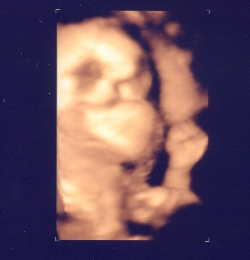

横顔、口の前でグーって握ってます

横顔、こちらはちょっと開いている手